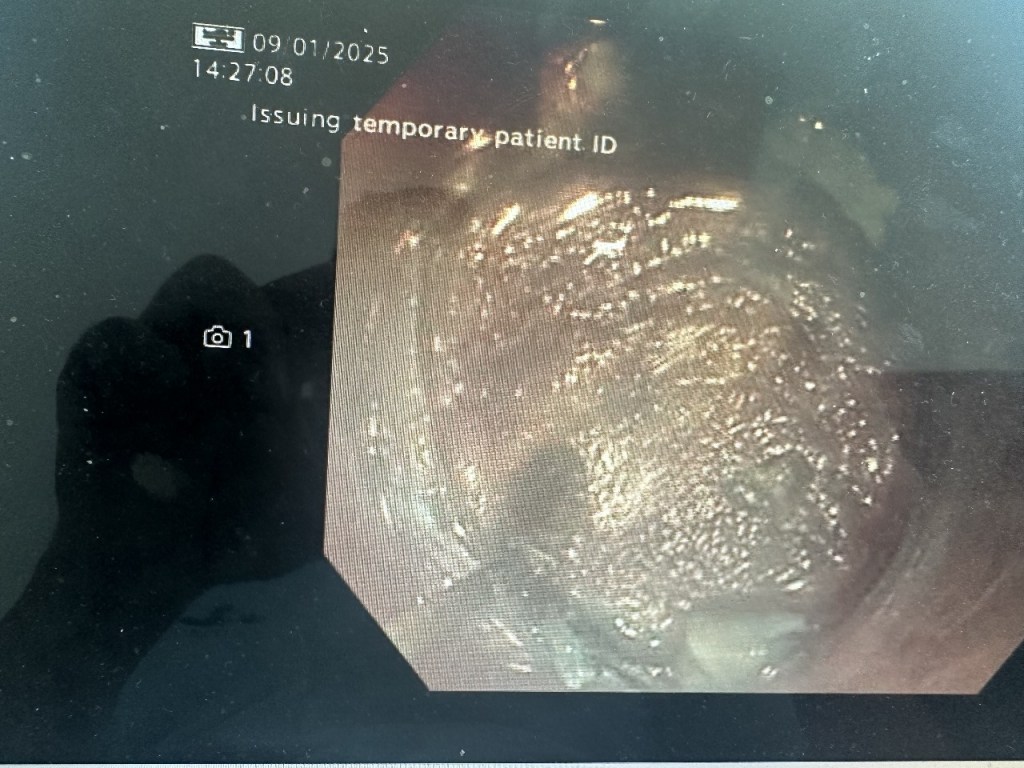

Determined to improve her quality of life, she opted for the Z-POEM (Zenker’s Peroral Endoscopic Myotomy) procedure, an advanced technique that eliminates the obstruction without open surgery. Dr. Gaurav Muktesh, Consultant Gastroenterologist, skillfully performed the procedure, using endoscopic techniques to divide the diverticulum’s septum.

Within 48 hours, the patient was back on her feet and able to eat without difficulty. A follow-up barium swallow confirmed that her esophagus was now functioning normally.